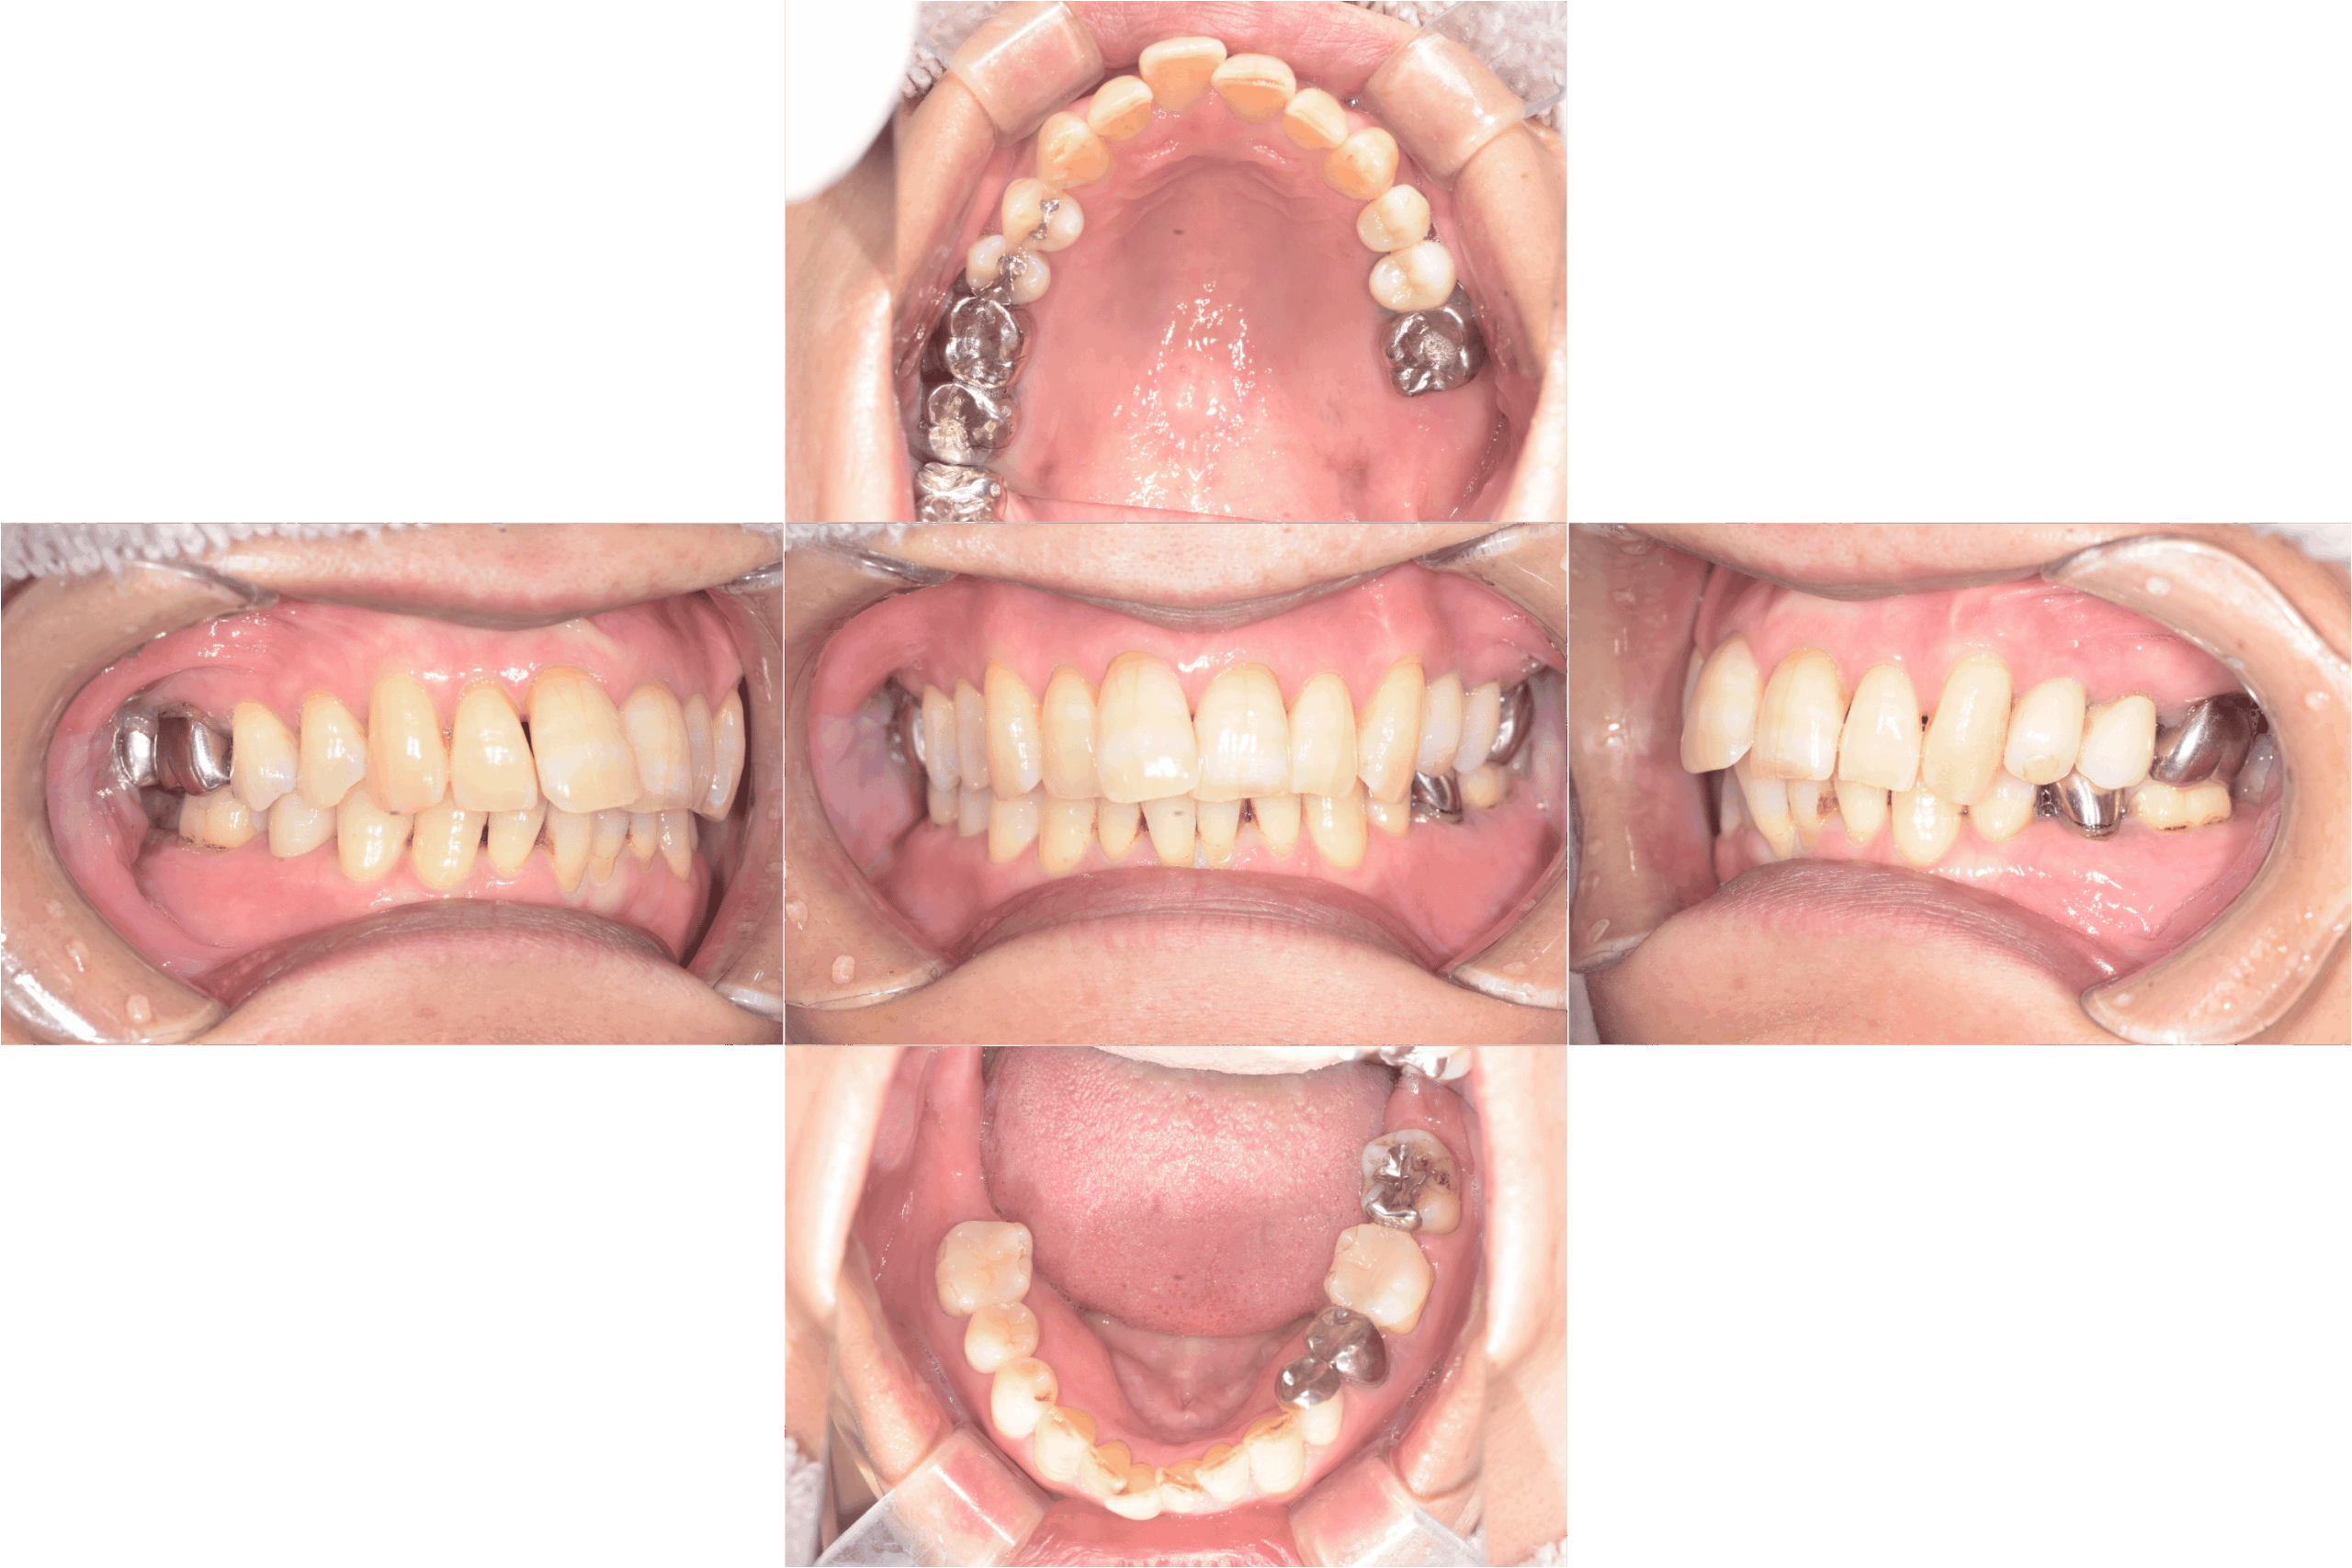

治療前口腔内写真